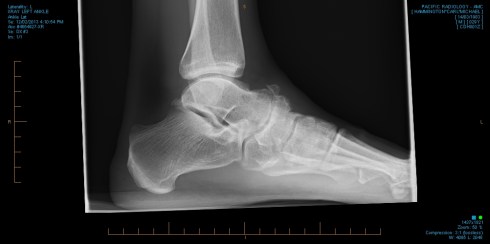

So to Carl, you may recall that although Carl’s assessment was more simple that Helen’s, he had some discomfort across the front of his left ankle and foot, especially when doing longer runs. This has been niggly for a few years.

Well the x-ray has shown what we suspected clinically, he has moderate to severe degeneration, but surprisingly also an ununited fracture through his Left Navicular bone. He is still adamant that he has had no major injuries to this ankle, but does recall a twist and pop whilst playing rugby a few years back but did not recall missing any games. He was very active when younger, being an age grade body building champion as well as training and playing rugby, so it may be that this is a stress fracture related injury to the Navicular. As a body builder he was on a high protein diet, though rarely used protein drinks.  Perhaps if the diet wasn’t balanced at the time this may have contributed to some mineral loss.  He has never taken any anabolic steroids.

As this foot /ankle been bothersome for a few years, but not too bad now and allowed him to do the ‘madness on Sunday he is still keen to progress and continue his training towards the Spartan. We have referred him to an orthopaedic surgeon for an opinion however, but at this stage it is still green light. It does prove what we see clinically, that although x-rays can be a useful tool, they do not always correlate with the patient’s symptoms.